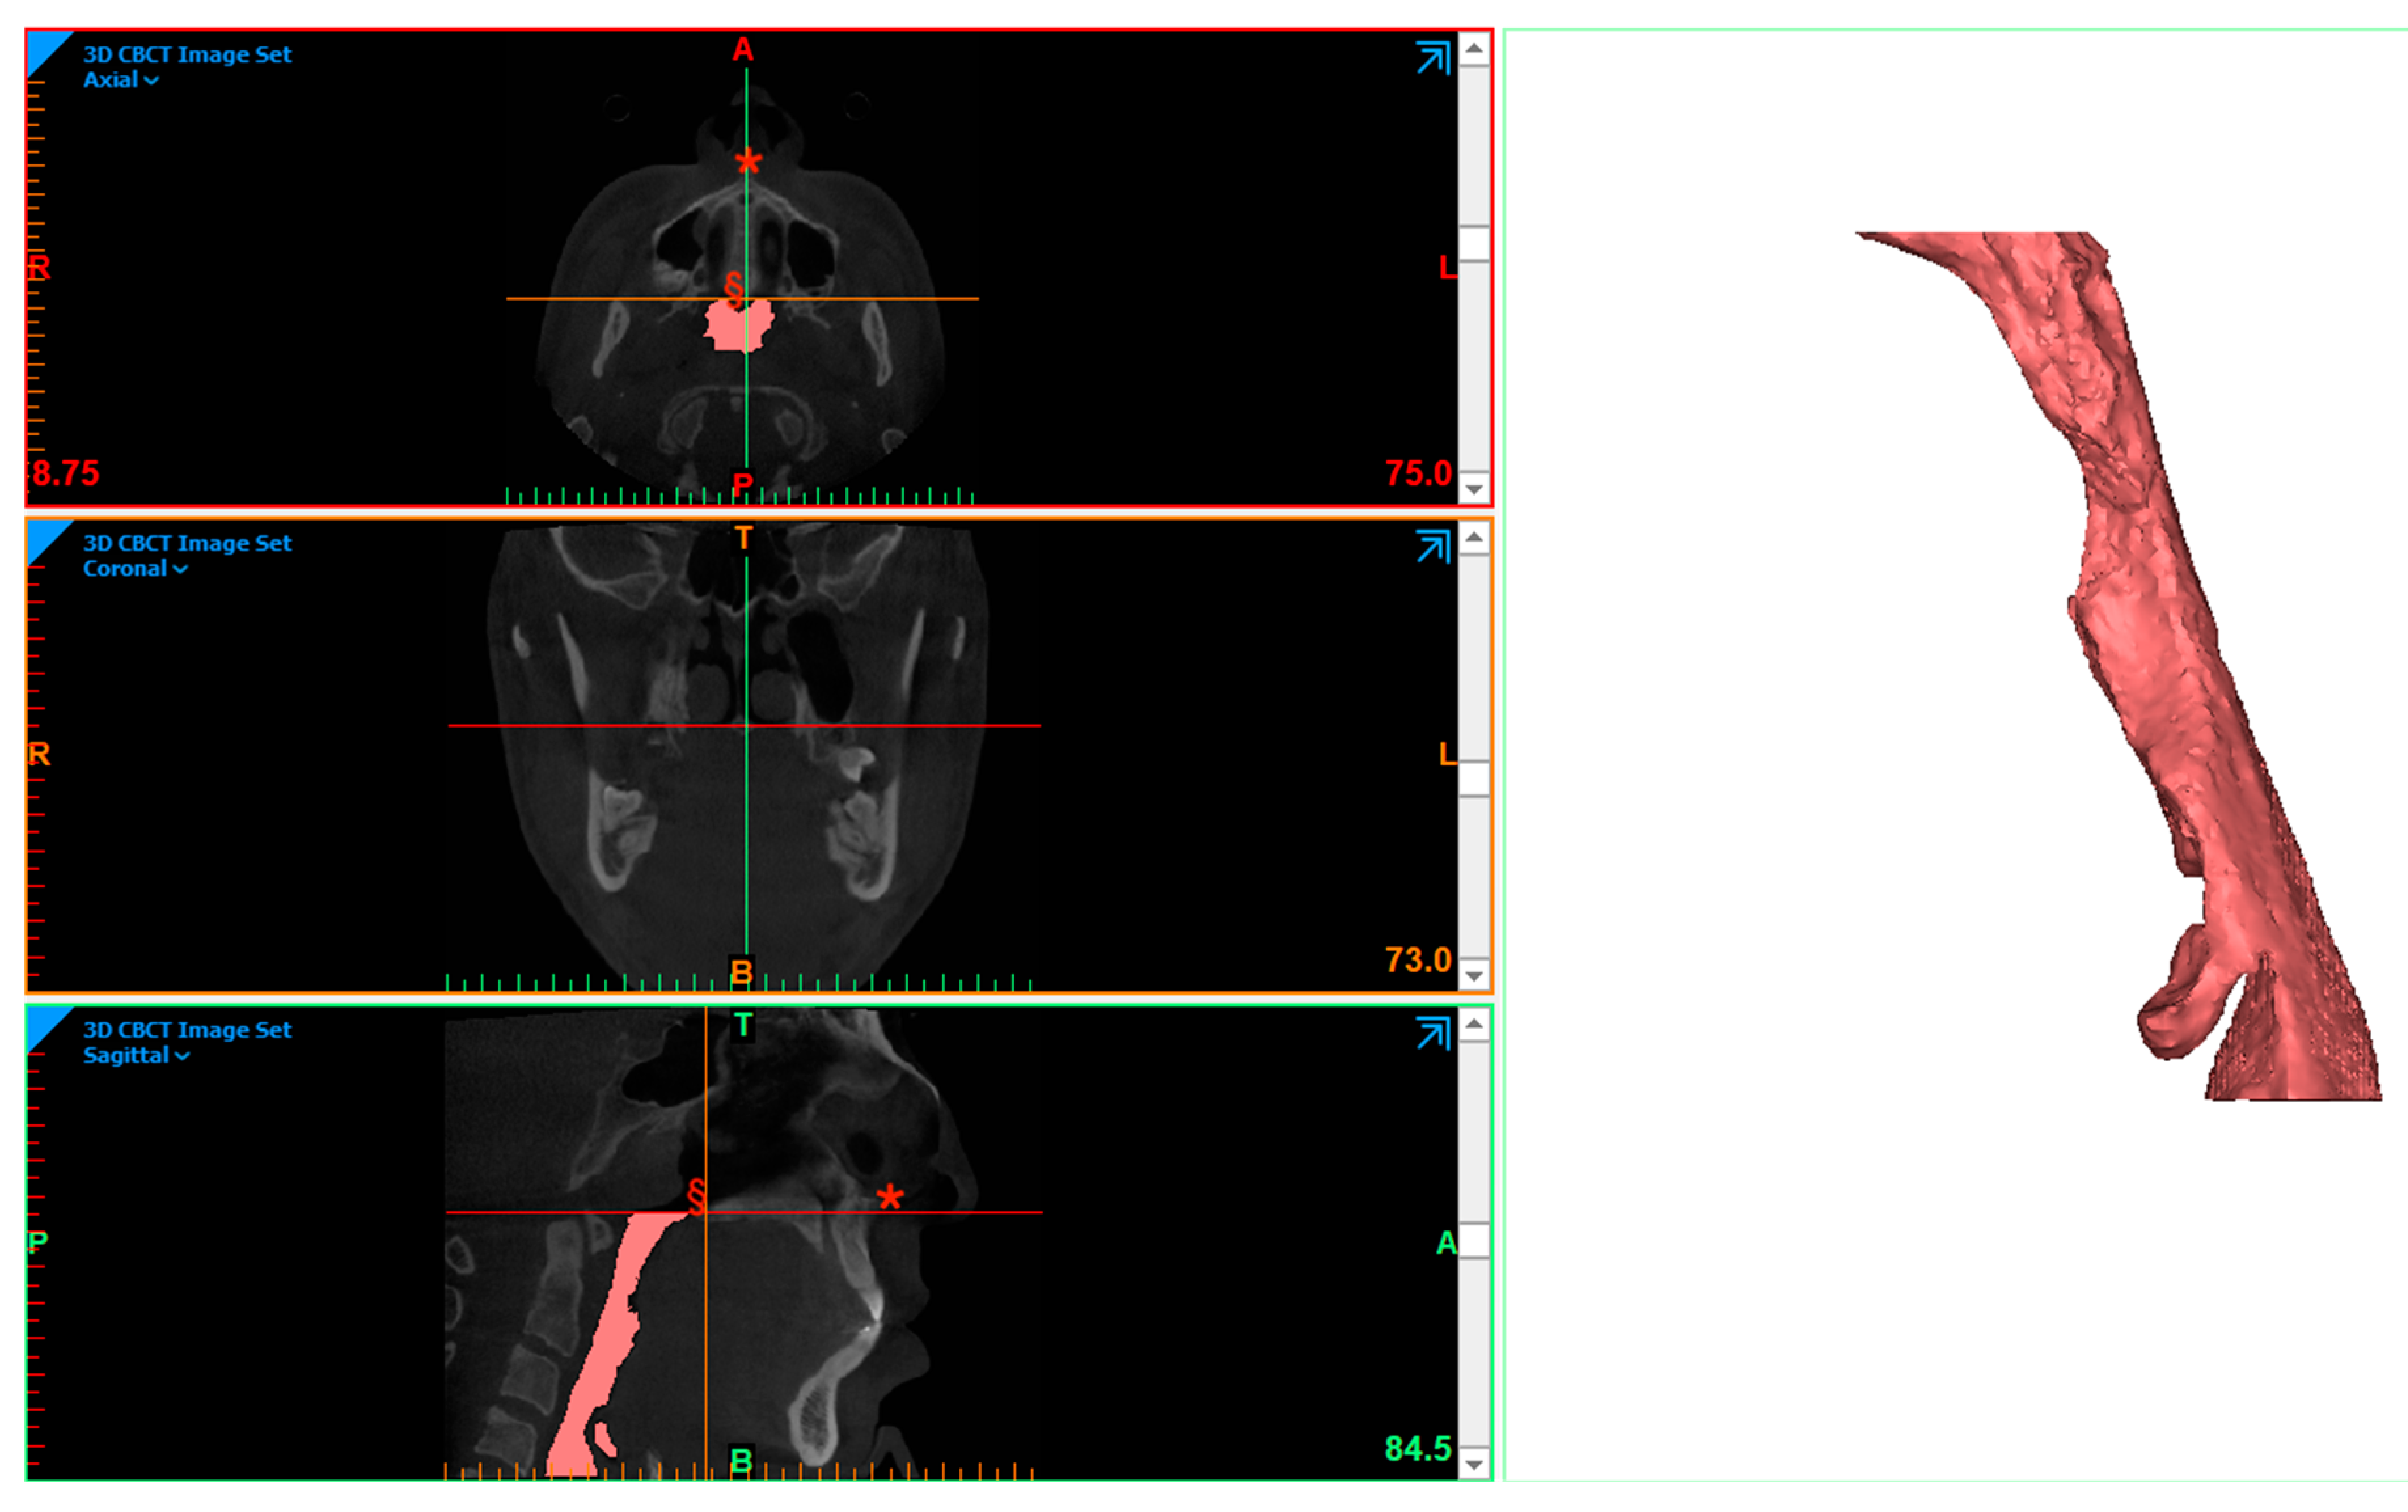

As with all orthognathic patients undergoing virtual surgical planning with PSI (patient-specific implant) production (e.g., cutting guide and fixation plate), CBCT images of the maxillofacial bones were collected before and 6 months after surgery. All patients benefitted from pre-operative orthodontic treatment in order to improve the occlusal results, and digital intra-oral scans were obtained at the end of this treatment. The STL and DICOM files were merged in order to plan the virtual surgery using the web based application PROPLAN CMF Online 4.0 (DePuy/Synthes (Synthes Inc., 1302 Wrights Lane East, West Chester, PA, USA) in cooperation with Materialise NV, Technologielaan 15 B-3001 Leuven, Belgium) (Figure 1).

Figure 1. Virtual simulation of MMA (patient N°4).

Figure 2. PAS segmentation session on CBCT; *: ANS; §: PNS (patient N°4).